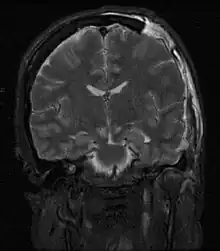

MRI showing damage due to herniation. This patient was left with residual disabilities including those involving movement and speech.[16]

Treatment involves removal of the etiologic mass and decompressive craniectomy. Brain herniation can cause severe disability or death. In fact, when herniation is visible on a CT scan, the prognosis for a meaningful recovery of neurological function is poor.[2] The patient may become paralyzed on the same side as the lesion causing the pressure, or damage to parts of the brain caused by herniation may cause paralysis on the side opposite the lesion.[11] Damage to the midbrain, which contains the reticular activating network which regulates consciousness, will result in coma.[11] Damage to the cardio-respiratory centers in the medulla oblongata will cause respiratory arrest and (secondarily) cardiac arrest.[11] Investigation is underway regarding the use of neuroprotective agents during the prolonged post-traumatic period of brain hypersensitivity associated with the syndrome.[17]